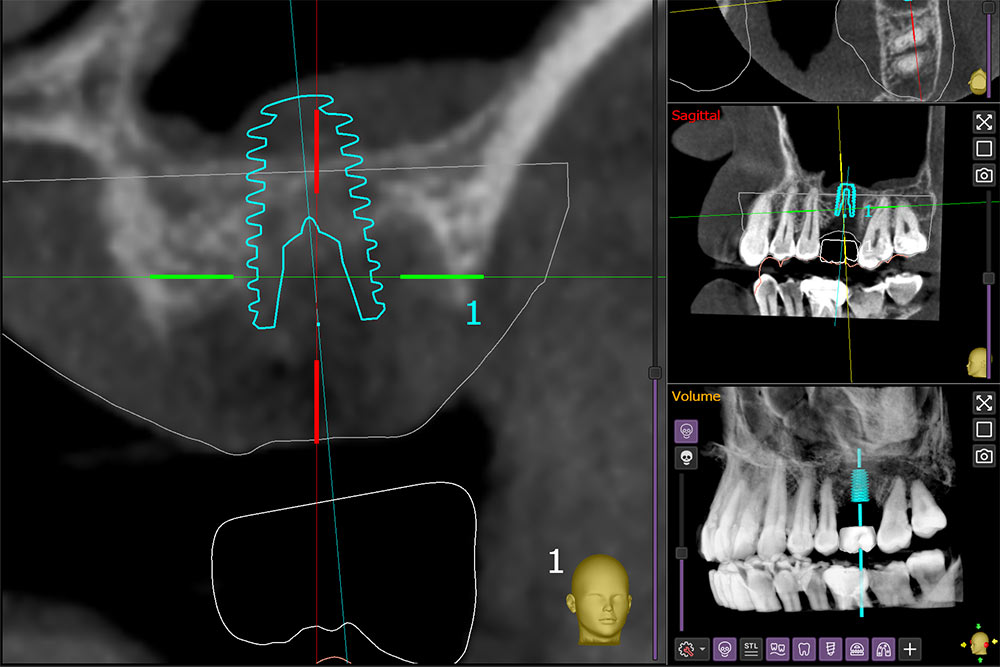

A sinus lift is only needed if there isn’t enough bone in the upper back jaw to hold an implant securely. During your consultation, a 3D CT scan is taken to measure the distance to the floor of the sinus.

Guided 3D planning and minimally invasive surgical techniques help ensure the procedure is safe, precise, and as comfortable as possible.

The choice of surgical approach depends on your individual jaw structure and the amount of bone available. Using a CBCT 3D scan, Dr. Amenien will carefully assess your situation and guide you toward the most suitable technique to ensure safe treatment and the best long-term results.